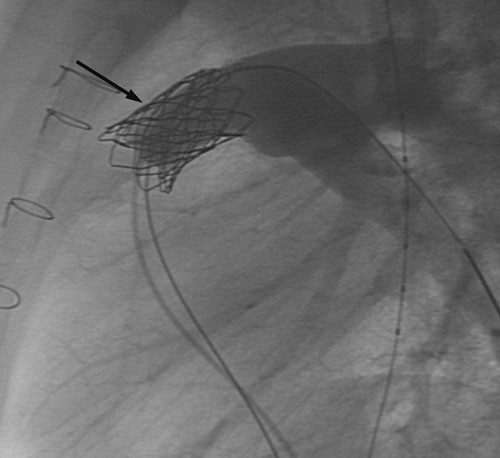

Kateteriseringsprosedyren blir gjennomført i samsvar med anbefalingene fra ledende internasjonale sentre og fra produsenten av perkutane kateterbaserte klaffer (7, 8). Pasientene er rutinemessig i generell anestesi under hele prosedyren, og det gis heparin intravenøst 100 IE/kg ved oppstart, etterfulgt av mindre påfyllingsdoser dersom prosedyren varer mer enn én time. Det gis antibiotika (Keflin 30 mg/kg) som en engangsdose. Det blir først foretatt en alminnelig høyresidig hjertekateterisering med tilgang fra lyskevene eller halsvene, trykkmålinger i høyre atrium, høyre ventrikkel og lungearterien, og angiografi med kontrastinjeksjon i høyre ventrikkel. Dette gir informasjon om stenose- og insuffisiensgrad i høyre ventrikkel-utløp, og også en detaljert anatomisk fremstilling av det området der den kunstige pulmonalklaffen skal forankres; sistnevnte har stor betydning for at prosedyren skal bli vellykket (fig 1). Med tilgang fra femoralarterie utføres dessuten koronarangiografi for å forsikre at koronararteriene ikke avklemmes når stenten plasseres i pulmonalutløpet.

Den kunstige pulmonalklaffen er fremstilt av halsvene fra kalv; klaffene i disse venene har en trikuspid anatomi som har stor likhet med humane pulmonalklaffer (8). Etter preparering i glutaraldehyd er venestump med klaff montert inn i en metallstent og forankret i denne med tallrike mikroskopiske suturer. Dette produktet (Melody, Medtronic, California, USA) kan komprimeres og føres inn i høyre ventrikkel-utløp gjennom et spesialdesignet kateter. Når rett posisjon oppnås, blir stenten med påsydd klaff ekspandert ved hjelp av ballonger slik at ytterveggene i stenten presses kraftig mot innsiden av høyre ventrikkels utløp. Dermed utvides utløpet, samtidig som stenten med klaff blir forankret. Trykkmålinger og angiografi etter innsetting blir brukt for å evaluere resultatet av prosedyren (fig 2). Alle stegene i denne prosedyren er utført i henhold til retningslinjer utarbeidet gjennom en serie europeiske møter gjennomført i regi av produsenten, og med deltakere fra alle de store sentrene i Europa. Vårt fagmiljø har bidratt aktivt i denne møteserien.

Innsetting av kunstig pulmonalklaff medførte signifikant lavere systolisk trykk i høyre ventrikkel hos samtlige pasenter; medianverdien ble redusert fra 60 mm Hg til 38 mm Hg (tab 3). Samtidig steg det diastoliske trykket i pulmonalarterien etter prosedyren hos et flertall av pasientene (tab 3, medianverdien er likevel den samme pga. liten spredning i materialet), og kontrastinjeksjon viste ingen eller minimal pulmonalinsuffisiens (fig 1 og 2). Median liggetid i avdelingen var to dager (maksimal liggetid fire dager for én person); pasientene ble deretter skrevet ut til hjemmet.